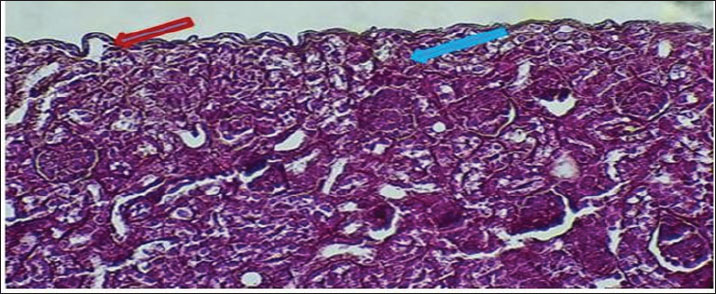

Figure 6 shows that the maturation of kidney tissue was visible on the later low-power H&E section of the 2-week-old hamster kidney compared with the 1-week specimen. The red arrow indicates how the renal cortex parenchyma is arranged, and the tubular regions are increasingly gathered and distinguished. Because the glomerulus was better developed, there was a clearer and bigger outline of the renal corpuscle. The yellow arrow marks the tubules that have been collected, and they now have distinct profiles and clear lines between epithelial cells, showing that urine concentration is starting and nephron structures are also dividing further. Figure 7 (Section Masson) implies that the capsule of the kidney cortex has received more fibrous support than in the previous stages. Columnar epithelial cells (marked by the blue arrow) were longer and better arranged in the inner part of the sac than they had been a week ago. The red or pink epithelial layer and the cytoplasmic structure were clearer from the blue collagen, indicating the formation of different tissue compartments in the body. Figure 8 presents the appearance of a hamster’s ureter at 2 weeks, stained with H&E in Figure A and with Alcian blue in Figure B at both 10x and 20x magnification. The lumen (red arrow) was slender and surrounded by a better-defined epithelial lining in both images. Simple squamous epithelial cells are marked by the yellow arrow in the transitional epithelium, and the blue arrow indicates a smooth muscle layer below. Mucosubstances in the epithelial layer became more noticeable in panel B because the Alcian blue stain was used, suggesting more mucus secretion for passing urine and shielding the bladder wall. Figure 9 includes two histological images of the renal cortex of a 3-week-old hamster. One was stained with hematoxylin and eosin (A) and the other with Masson’s trichrome (B) under 40x magnification. There was an increased formation of renal corpuscles in every area, where the capillary tufts were evident (yellow arrows). The red-marked proximal tubules have a well-formed brush border, and their cytoplasm is colored eosinophilic. Both images have blue arrows that confirm that the renal veins were connected with the blood vessels in the cortex. In Fig. 10, Panels A and B, Masson’s Trichrome (A) and Van Gieson (B) stains were used for transverse sections seen at 20x. The red arrows show where the unambiguous ureteral lumen was located. Simple squamous epithelium was highlighted by yellow arrows and stratified. The blue arrows denote the muscles found in the area, whereas the black arrow in panel B marks the pink layer seen on the outside called the serosa. Currently, the ureter looks complete, as confirmed by its multilayered structure, and is ready. Fig. 11 shows the renal cortex from a 2-month-old hamster stained with PAS (A, 20x) and H&E (B, 40x). Panel A shows that the renal capsule is organized and composed of fibrous tissue. The yellow arrow indicates that the advanced renal corpuscle has a distinct Bowman’s space, and the blue arrow indicates a major proximal tubule marked by its brush border and PAS-positive basement membrane. The black arrow indicates the wider lumen and the pale cytoplasm of the distal tubule. In the H&E image, the two main kinds of tubules were easily identified, proving that the nephron has developed completely and matured in the cortex. At a magnification of 40x, the renal corpuscle is clearly seen in Masson’s Trichrome (A) and Van Gieson (B) stained slides, as shown in Fig. 12. The blue arrows show complete glomerular capillaries that were properly perfused and assigned a consolidated mesangial matrix. These arrows were aimed at the juxtaglomerular cells on the vascular side, indicating that they were ready to release renin. The red arrows show the urinary pole and the proximal tubule entrance, indicating that the nephron was intact. The black arrows indicate sections of the tubules that lie far from the glomerulus. They also highlight how the nephron is made up of important sections and how the corpuscle becomes an effective filtration unit. Fig. 13 shows a sliced ureter in a 2-month-old hamster demonstrating that its structure was fully mature by Masson’s Trichrome (A) and Van Gieson (B) staining. The red arrows show a wideness to the ureter, proving that the epithelial and muscular layers have healed well. The yellow arrows point to a fully developed urothelium and show simple squamous to cuboidal features according to the ureter location. The thicker and more organized circular muscle groups were observed, where the blue arrows were found inside the walls.

Fig. 6. Cross-hematological sections of kidney hamsters aged 2 weeks showing cortex parenchyma tissue (red arrow) and renal corpuscle (blue arrow) collected tubules (yellow arrow). 10x. H&E.

Fig. 7. Cross-section of kidney cortex at 2 weeks of age showing two layers of connective tissue capsule (red arrow) and sub capsular simple columnar epithelium (blue arrow). 20x. Masson’s trichrome stain.

Fig. 8. Cross-histological section of the ureter in hamsters aged 2 weeks showing a mild lumen (red arrow) in the middle, simple squamous epithelial (yellow arrow), smooth muscle A-10x H&E stain B- 20x. alcian blue.

Fig. 9. Cross-histological section of the renal cortex in hamsters aged 3 weeks. Renal corpuscle (yellow arrow), junction of glomeruli capsule with proximal tubule (red arrow), and renal vein (blue arrow). A- 40x H&E stain, B- 40x. Masson’s trichrome stain.

Fig. 10. Cross-histological section of the ureter in hamsters aged 3 weeks showing a hollow lumen (red arrow) in the middle, a simple squamous epithelial layer (yellow arrow), smooth muscle (blue arrow), and serosa (black arrow) A-20x Masson trichrome stain, B- 20x. van -gison stain.

Fig. 11. Cross-histological section of the renal cortex in hamsters aged 2 months, consisting of the capsule (red arrow), distinct renal corpuscles (yellow arrow), and proximal tubule (blue arrow) and distal tubule (black arrow). A- 20x. PAS stain. B- 40x. H&E.